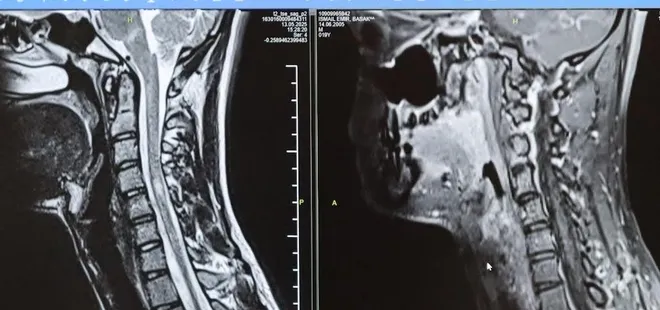

Uzmanlar, Multiple Skleroz (MS) hastalığının her bireyde farklı belirtilerle seyredebildiğine dikkat çekiyor. Tedaviye hastalığın erken aşamalarında başlanmasının, hastaların günlük yaşam kalitesini korumasında büyük önem taşıdığı vurgulanıyor.

MS (Multiple Skeleroz) hastalığının her bireyde farklı bir şekilde gelişebileceğinin altını çizen Nöroloji Uzmanı Prof. Dr. Özden Kamışlı, tedaviye erken aşamalarda başlandığı takdirde hastaların günlük hayatta yaşam kalitelerini koruyacağını belirtti.

Bursa Şehir Hastanesinde görevli Nöroloji Uzmanı Prof. Dr. Özden Kamışlı, 30 Mayıs Dünya MS Günü kapsamında açıklamalarda bulundu. MS'in, bağışıklık sisteminin sinir sistemine saldırmasıyla gelişen kronik bir hastalık olduğunun bilgisini veren Prof. Dr. Kamışlı, "Dünyada yaklaşık 2.8 milyon MS hastası olduğu bilinmektedir. MS genellikle 20-40 yaş arası gençleri etkilemektedir. Bununla birlikte çocukluk döneminde ya da ileri yaşta da ortaya çıkabilmektedir. Kadınlarda görünme sıklığı erkeklere göre bir buçuk kat daha fazladır" dedi.

MS hastalarının çeşitli şikâyetlerle hekimlere başvurduğunu vurgulayan Kamışlı, "Bunlar arasında görme bozukluğu, kol ve bacakta kuvvetsizlik, uyuşmalar, dengesizlik, yürüme bozukluğu, idrar problemleri veya aşırı yorgunluk ve halsizlik hali bulunmaktadır. MS ataklarla seyredebilir ve genellikle en sık görülen formu budur. Birdenbire bir şikâyet ortaya çıkar ve zamanla azalır veya kaybolur. Bir de progresif dediğimiz ilerleyici formu vardır. Bu ilerleyici formda hastalık yavaş yavaş ilerlemektedir. MS her hastada farklı seyreder. Bu nedenle tek tip bir MS hastalığından bahsetmek mümkün değil" şeklinde konuştu.

Tedavide gelişme kaydedildi

Hastalığın tanısını ne kadar erken konulursa ve tedaviye ne erken başlanırsa; hastaların günlük hayatta aktif ve üretken bir şekilde devam etmelerinin o kadar kolaylaştığına dikkat çeken Kamışlı, "Günümüzde MS'le ilgili çok fazla gelişme oldu ve tedavi seçenekleri arttı. MS merkezlerinde bu tedavi seçeneklerine ulaşmaları mümkün. Hastalarımız için doğru tanı, düzenli takip ve uygun tedavi oldukça önem teşkil etmektedir" diye konuştu.